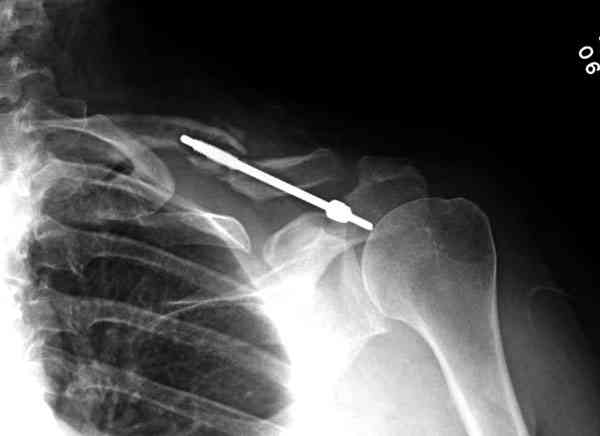

ГГШ> Результат стационарного лечения приведен на рентгенограмме (Xray_3).

2) стояние фрагментов при выписке идентично таковому при пступлении - с выраженным смещением

Ув. Г.В.! На мой взгляд, никакого ухудшения стояния отломков на втором снимке нет!!! Просто проекция среднего снимка несколько под другим углом, и увеличение межотломкового расстояния не что иное , как проекционное искажение. По - поводу колец... Конечно они иммобилизуют плечо лучше , чем Cuff and Collar, хотя не намного, но что если разовьётся парез брахиального сплетения???

Уважаемая Г.В. Полностью согласен с Вашим постом.Закрытая репозиция и кольца Дельбе отлично зарекомендовали себя за 35 лет практики. В обсуждаемом случае представленные Р-граммы сами говорят за себя, 1 снимок (до лечения) и 3 снимок (после лечения) абсолютно идентичны, 2 снимок сделан в несколько иной позиции.Как говорится "комментарии излишни". Согласитесь, что результат лечения мог бы быть и лучшим.